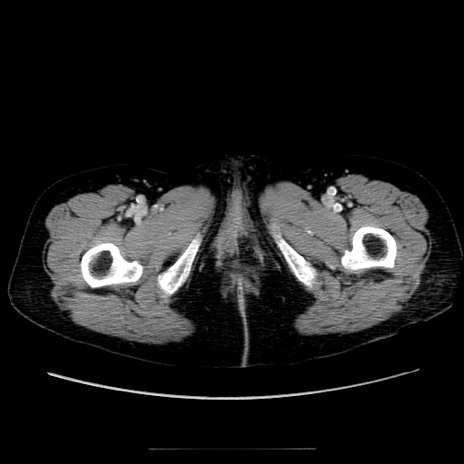

【症例】70歳代女性

【主訴】お腹が張る

【現病歴】1週間くらい前から腹部膨満の自覚あり。昨日夜から増悪したため、本日救急外来受診。

【身体所見】意識清明、BT 36.5℃、BP 165/106mmHg、HR 80bpm、SpO2 98%、腹部:膨満、軟、自発痛・圧痛なし、触診にて不快感あり、腸蠕動音:減弱

【データ】WBC 12600、CRP 1.04